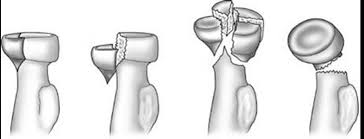

Qu est ce que la fracture de la tête radiale?

Il s’agit d’une fracture la partie la plus proche du coude de l’os appelé radius.

Comment se traite une fracture de la tête radiale ?

En fonction du type de fracture, le traitement peut consister en :

- une immobilisation le temps que la douleur s’atténue, pour les fractures enfoncement stables

- une chirurgie conservatrice (ostéosynthèse par vis ou plaque) pour les têtes radiales « réparables »

- Un remplacement prothétique (prothèse tête radiale) pour les têtes radiales « non réparables »